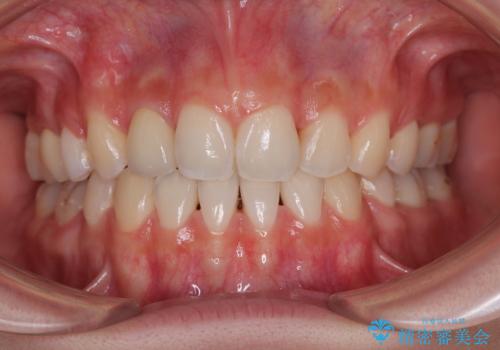

- 【モニター】とがった口元を抜歯して改善 ワイヤー装置の矯正治療- 担当医 藤巻太一朗